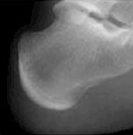

4) 같은 또래 아이들의 키보다 2표준편차 이상 작은 경우에는 성장클리닉 전문의의 진료가 필요합니다. 키가 정확히 또래 아이들보다 작은편인지 큰 편인지 진료를 통해 알아볼 수 있으며 성장판 촬영으로 골연령을 정확히 측정하는 것이 중요합니다.

| 열린경우 | 닫혀가는 경우 | 닫힌 경우 | |

| 종골 Calcaneus |

![]() |